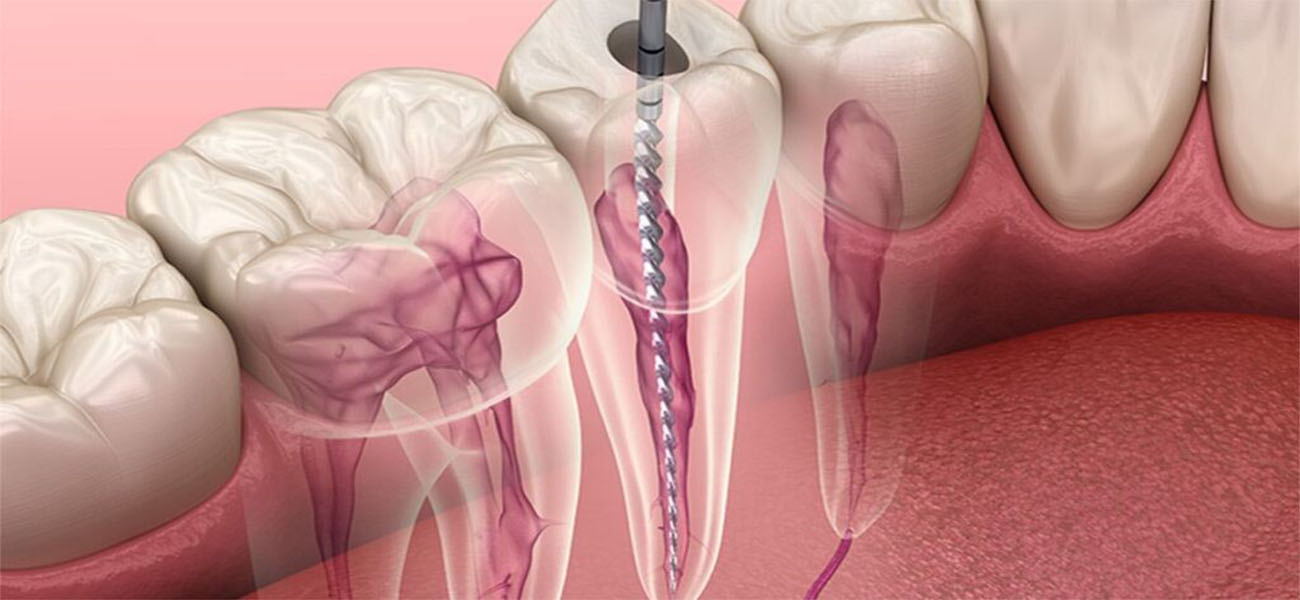

عصب کشی دندان (اندودنتیک) یک روش درمانی است که برای نجات دندانهای آسیب دیده یا عفونی شده انجام میشود. این روش شامل حذف بافت ملتهب یا عفونی از داخل دندان و پر کردن آن با مواد مخصوص است. عصب کشی به دلایل زیر اهمیت دارد:

3. حذف بافت آسیب دیده

در این مرحله، پزشک با استفاده از ابزارهای مخصوص، بافت ملتهب یا عفونی داخل دندان را حذف میکند.

4. پاکسازی و فرم دهی کانال ریشه

پس از حذف بافت آسیب دیده، کانال ریشه دندان تمیز و فرم دهی میشود تا آماده پر کردن باشد.

5. پر کردن کانال ریشه

در نهایت، کانال ریشه با مواد مخصوص پر شده و دندان ترمیم میشود.